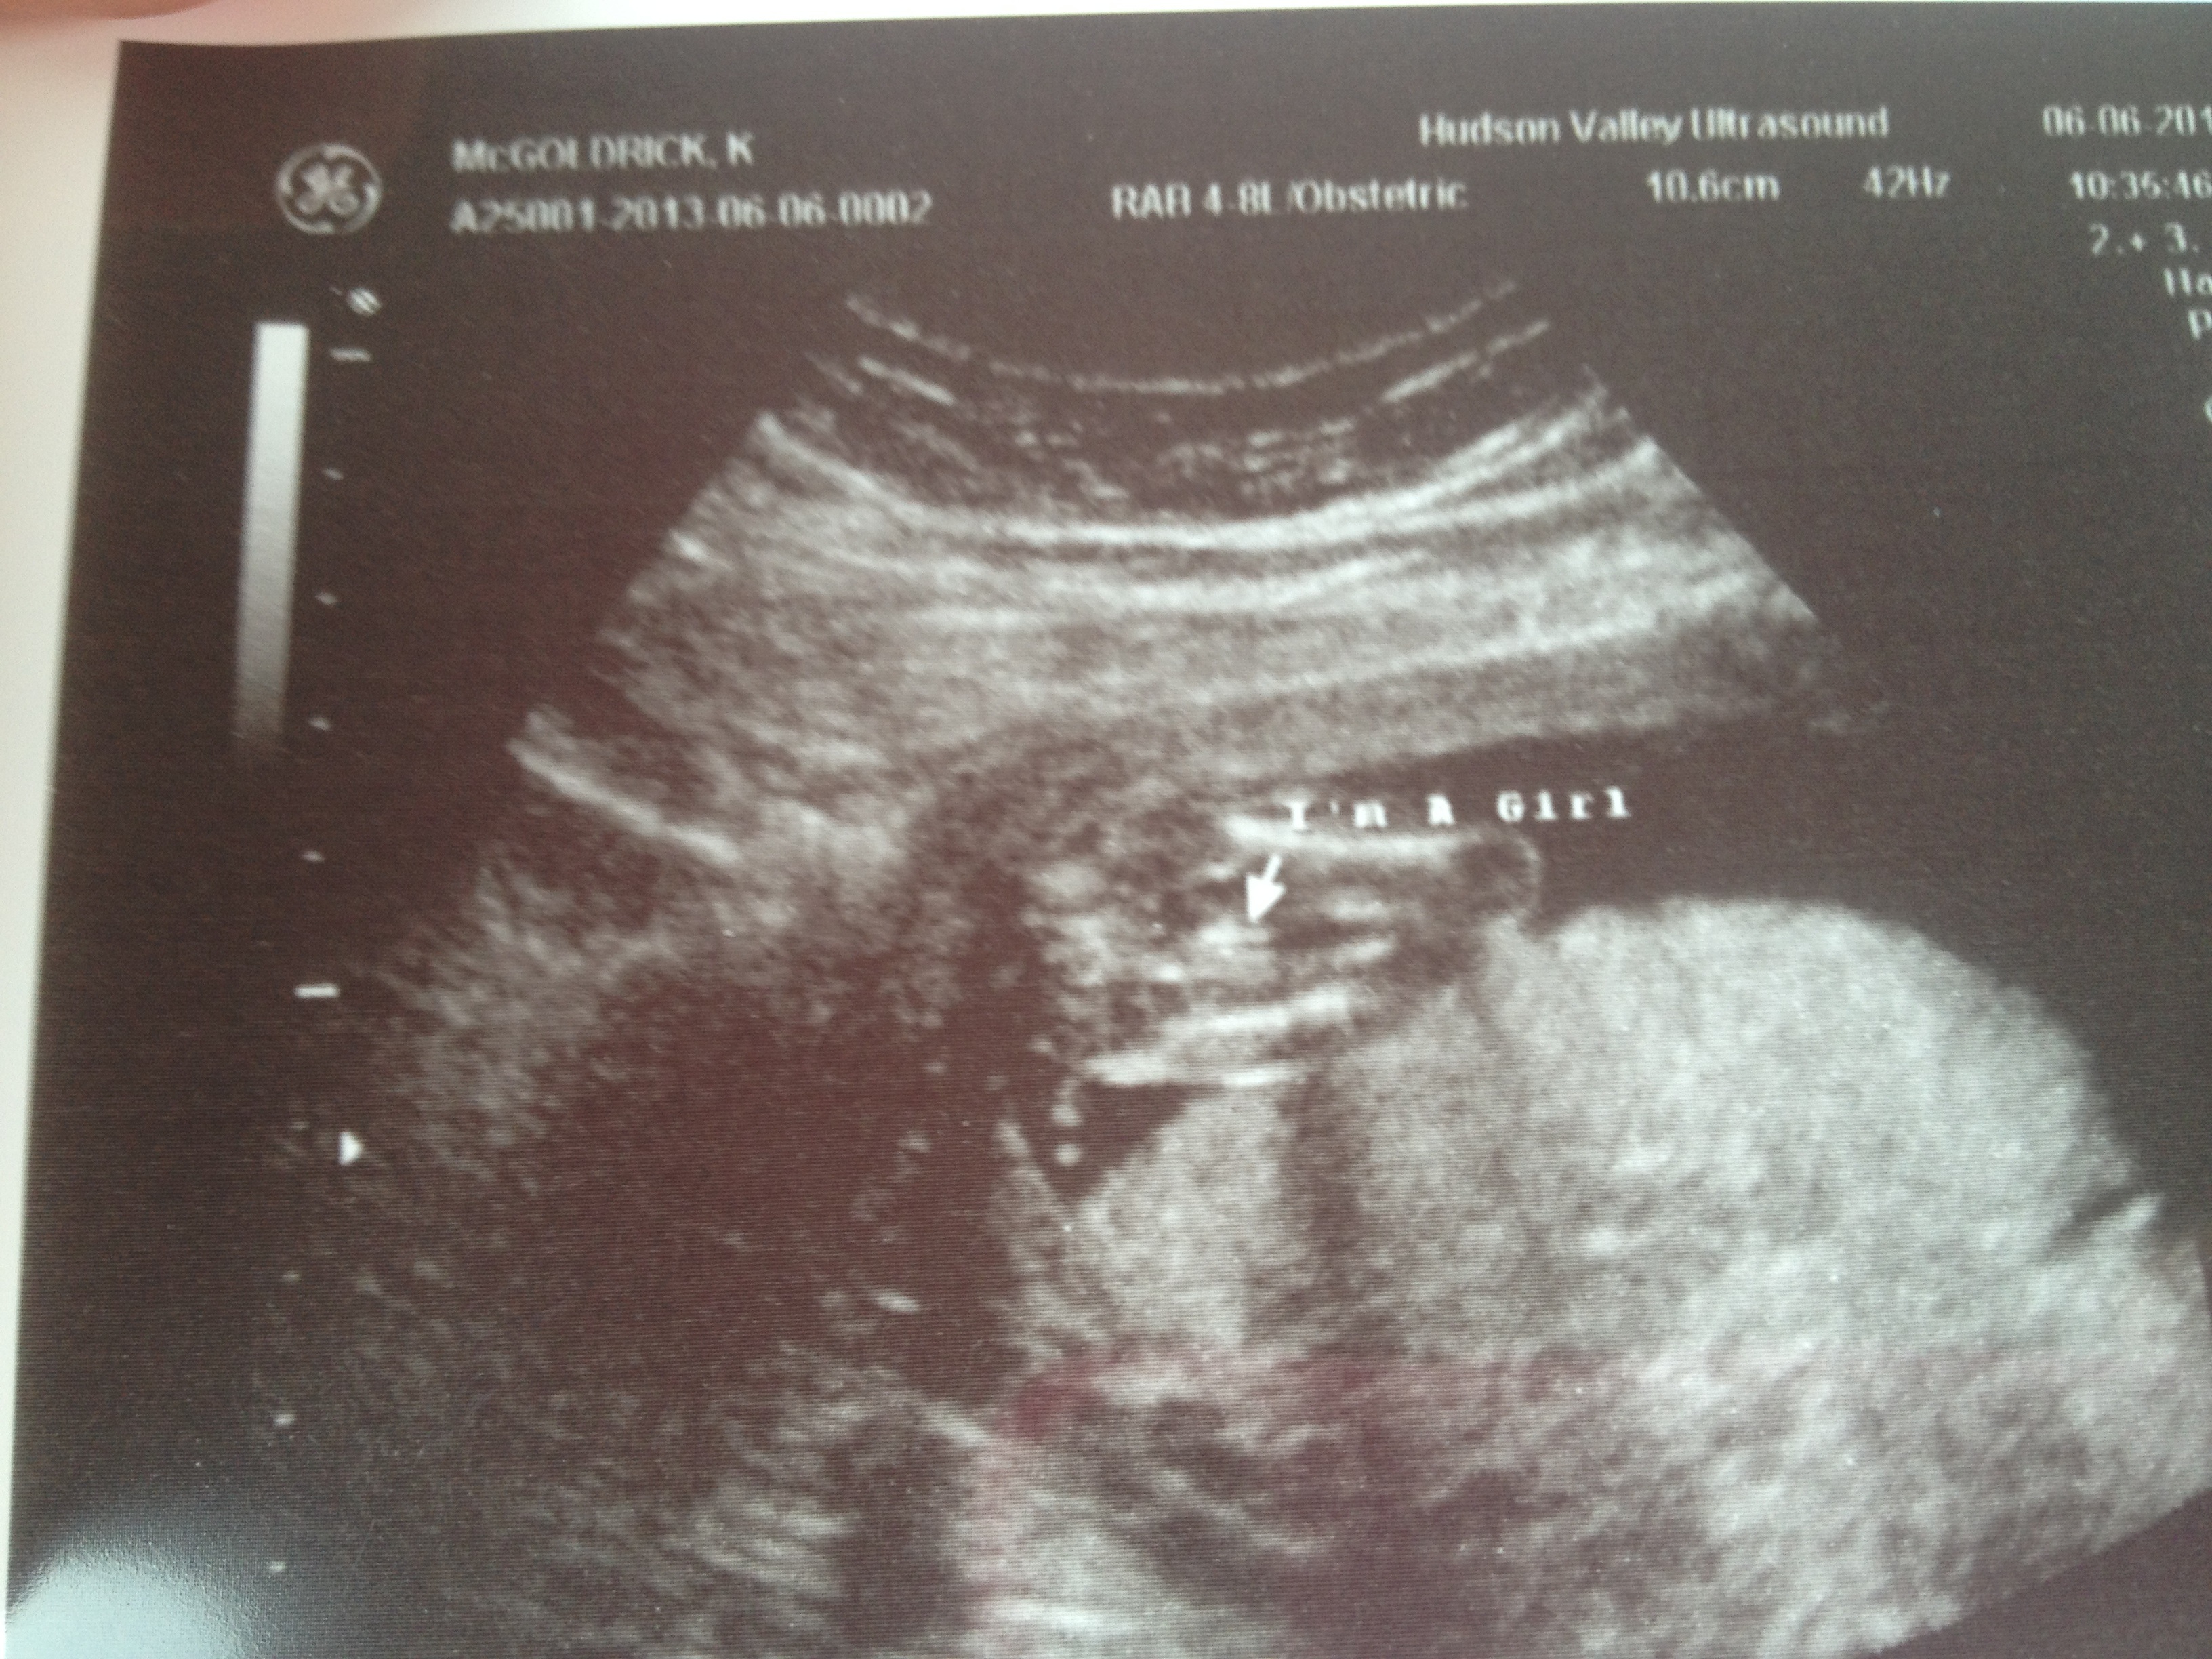

Had a u/s last week. I have 3 Boys and hoping the tech is right!

No clues in the first image. The legs are way too close together to see either boy or girl parts. The 2nd image, however, looks VERY promising for a baby girl. Congrats!

Second one, the nub, looks totally flat!